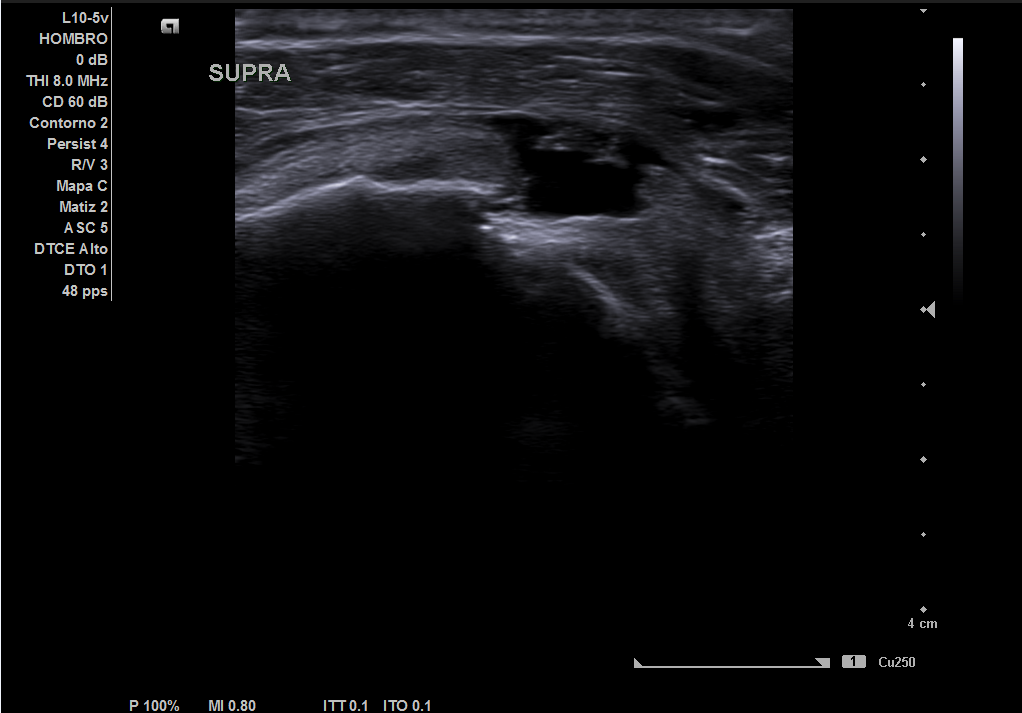

Descripción de los hallazgos ecográficos y las imágenes más relevantes para la resolución del caso

En la ecografía realizada observamos una rotura completa del tendón supraespino, rotura parcial del subescapular y severo derrame peritendón del bíceps junto con derrame articular glenohumeral.

Juicio diagnóstico: rotura manguito de los rotadores (rotura completa supraespinoso).